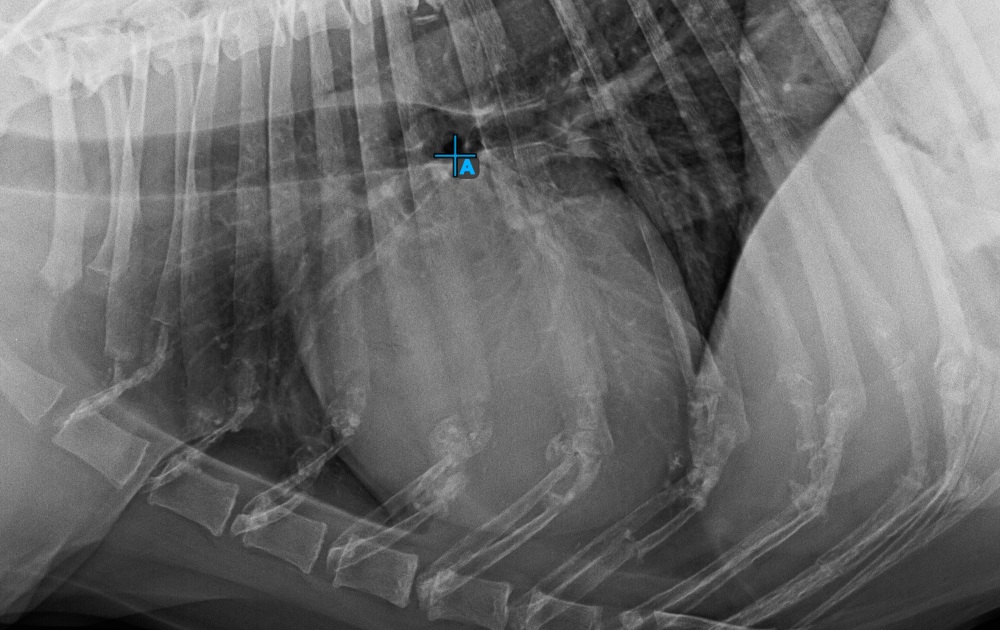

Vervollständigen Sie die Kurzachse des Herzens, indem Sie den breitesten linken (hinteren) Punkt markieren.

Das Bild unten zeigt die typische Platzierung des hintersten Punkts auf der Kurzachse des Herzens.